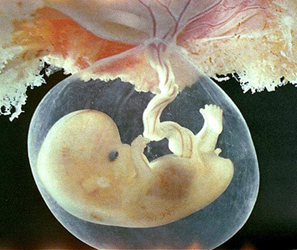

Сегодня наконец то были у врача,теперь мы стоим на учете!!!)))Анализов кучу навыписывали,врач сказала что матка хорошо растет,счастья....полные штаны...наш малыш РАСТЕТ!!!!через пару недель пойдем на узи))